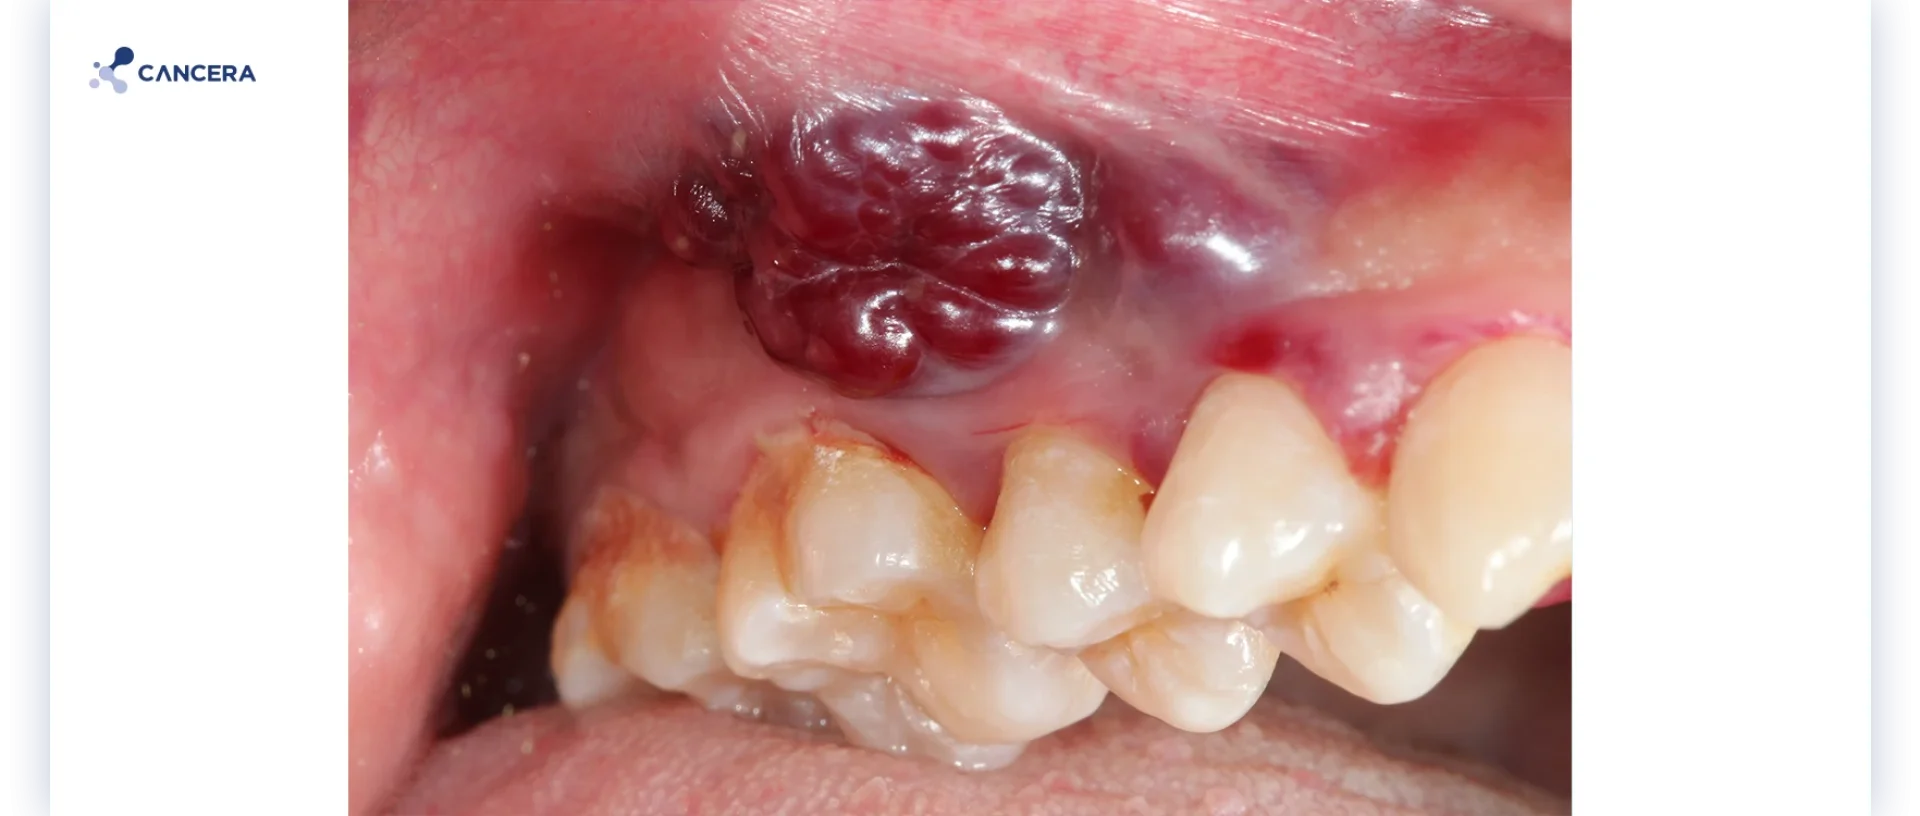

มะเร็งช่องปาก (Oral Cancer) เป็นเนื้อร้ายที่เกิดและพัฒนาขึ้นในส่วนใดก็ตามที่อยู่ในช่องปาก โดยเซลล์มะเร็งอาจเกิดขึ้นได้ทั้งที่บริเวณริมฝีปาก ลิ้น เหงือก กระพุ้งแก้ม เพดานปาก หรือพื้นปาก ในกรณีที่พบได้น้อย เซลล์มะเร็งยังสามารถเกิดขึ้นได้ที่ทอนซิลด้านหลังช่องปาก ซึ่งเป็นต่อมผลิตน้ำลาย รวมถึงในบริเวณช่องคอที่เชื่อมต่อระหว่างปากกับหลอดลมหรือคอหอย

- ที่บริเวณริมฝีปาก เหงือก หรือส่วนอื่น ๆ ในช่องปาก เกิดอาการบวม มีตุ่ม ก้อนเนื้อ หรือมีแผลเกิดขึ้น